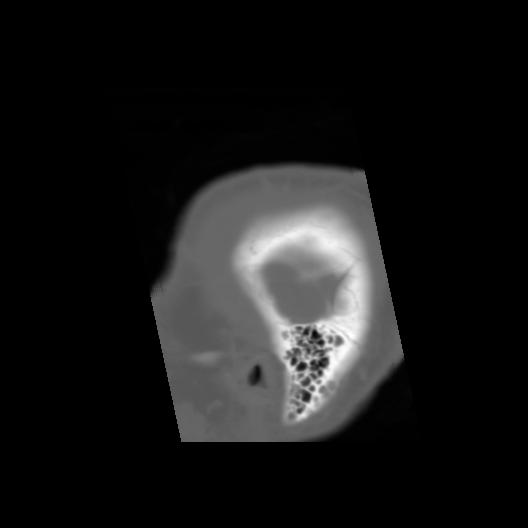

6 CEREBRO,,Sagittal,3.000,CEREBRO,Sagittal,